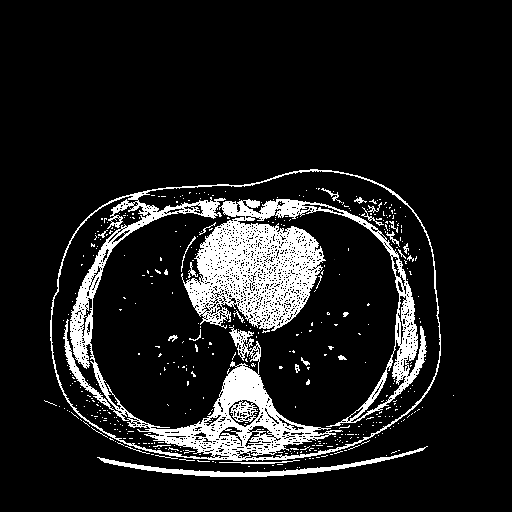

Original NATIVE CT scan (input)

Full window (WL 1023.5, WW 4095 β†’ Low βˆ’1024, High +3071)

Actual HU range: [-1024.0, 3071.0]